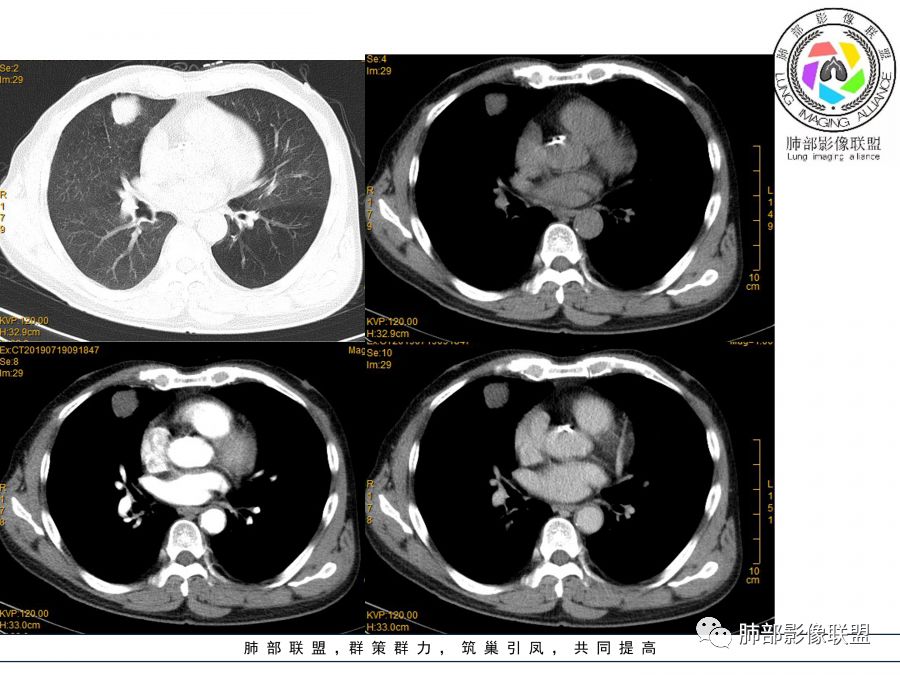

目测这里还是有强化,其余地方强化幅度不是很明显

中低分化鳞癌

1.右肺中叶孤立不规则块影,浅分叶,未见液化或钙化,未见毛刺,未见脐凹,未见明显胸膜牵拉。

2.近肺门侧隐约见支气管截止。

3.外侧可见血管进入,病灶局部轻度强化。

上述均不符合光滑类圆形的支气管肺囊肿,也不符合典型的类癌,切不可先入为主。也不符合转移瘤。

4.肺门纵隔未见增大淋巴结。如此体量的肺块,没有增大淋巴结,不符合小细胞肺癌的生物学行为。

5.未见卫星灶,未见支气管增厚,结核也缺少支持点。

综上,应当鉴别的主要为肺鳞癌及结核灶